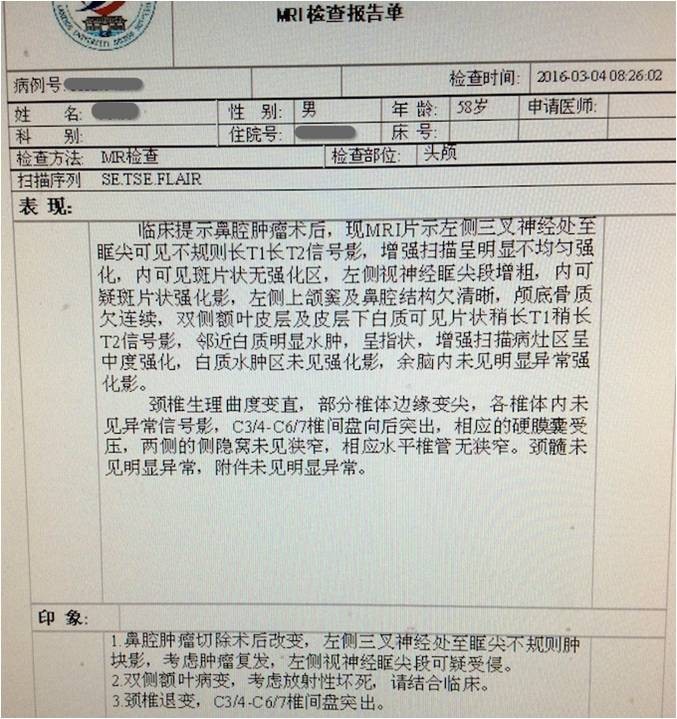

▼患者影像资料(2015-7-3)